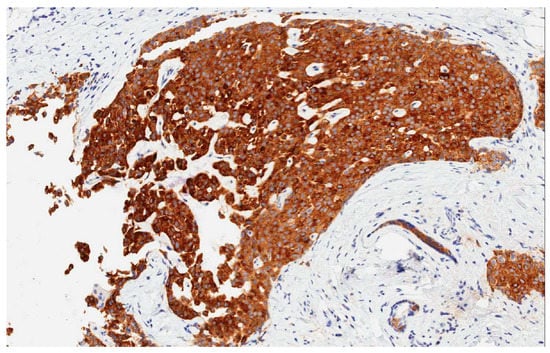

- The presence of over 50% of neoplastic cells expressing neuroendocrine markers of immunohistochemistry such as chromogranin A and synaptophysin (Figure 2). Neuron-specific enolase (NSE) and CD56 appear to result in lower sensitivity and specificity, mostly because they are normally present in breast tissue [2,5,6,11]. When the neuroendocrine characteristics are shown in less than 50% of cancer cells, the tumor should be identified as a breast cancer with neuroendocrine differentiation. The focal neuroendocrine differentiation within the carcinoma of the breast is common and has no prognostic significance.